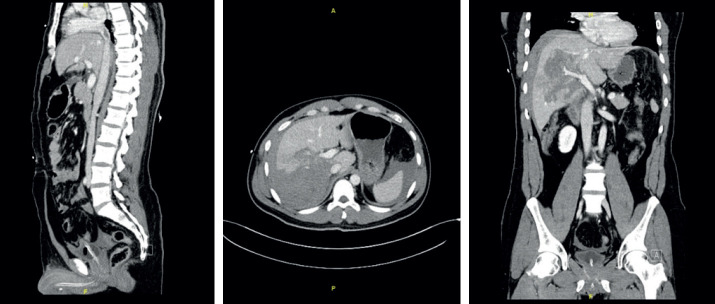

Background: Inferior vena cava thrombosis (IVC-Th) is a rare clinical entity after blunt abdominal trauma. It has both diagnostic and therapeutic dilemmas. Pulmonary embolism is the most dreadful complication and the leading cause of mortality after IVC-Th. Therefore, accurate prompt diagnosis is crucial.

Objective: The aim of this article was to present a case of IVC-Th in a young male patient who had a blunt traumatic abdominal injury after a motor vehicle accident.

Case presentation: The patient was brought to emergency department and was successfully managed by angio-jet thrombolysis. He developed a transient contrast nephropathy that was recovered after continuous renal replacement therapy. Several management options have been proposed in the literature, including conservative, endovascular and operative management.